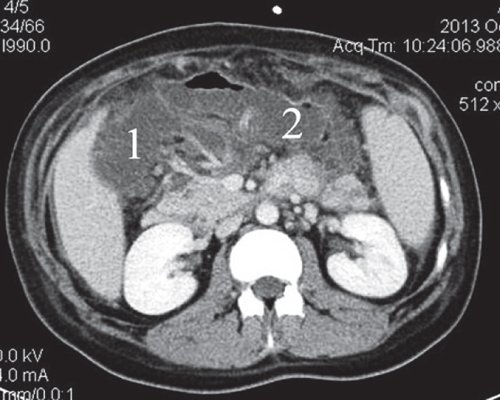

При проведении КТ брюшной полости установлено: в брюшной полости свободная жидкость (преимущественно по правому и левому флангам, поддиафрагмально слева). Печень не увеличена, форма и положение не изменены. Контуры ровные, четкие, структура паренхимы достаточно однородная, плотность не изменена. Внутри- и внепеченочные протоки не расширены. КТ-признаков очаговых и объемных образований не выявлено. В желчном пузыре мелкие конкременты. ПЖ выраженно диффузно неоднородной структуры, увеличена в размерах, контуры достаточно четкие. Вирсунгов проток - без признаков обструкции. В проекции сальниковой сумки визуализируется жидкостное образование пониженной эхоплотности, при введении контраста не накапливает контраст. В сальниковой сумке образование по типу инфильтрата. Заключение: "КТ-картина острого панкреатита. Инфильтрат сальниковой сумки. Псевдокиста ПЖ" (рис. 15, 16).

a) Нативная фаза. Жидкостное образование в сальниковой сумке (1), инфильтрат (2).

б) После контрастирования визуализируется плотная капсула жидкостного образования.